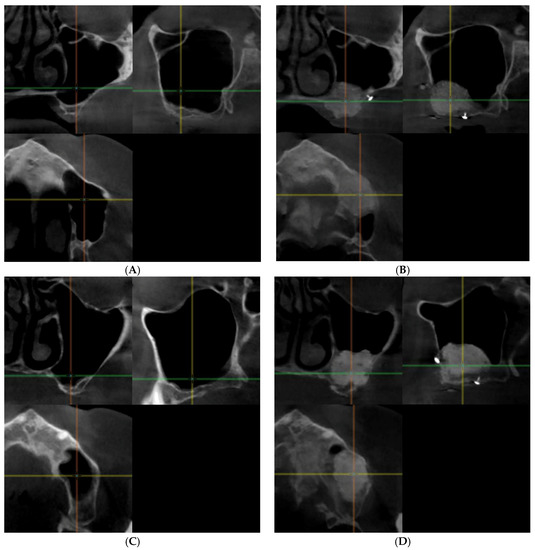

3.2.1. Qualitative Analysis of the μCT Images